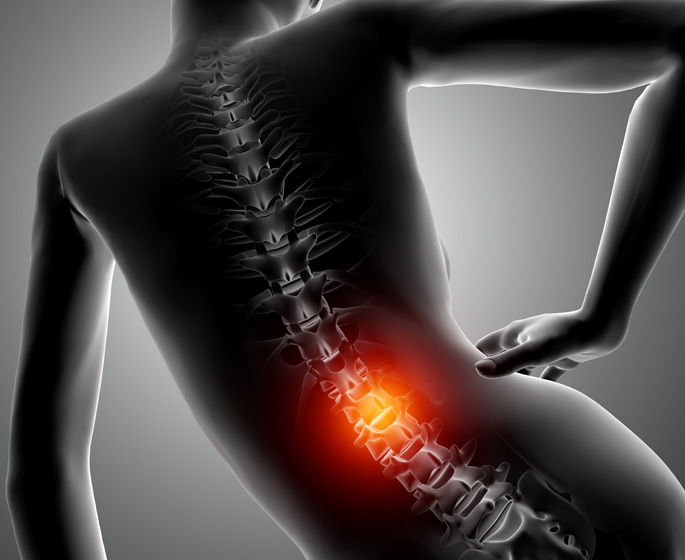

Bol u donjem dijelu leđa

Programi vježbanja su usmjereni na jačanje jezgra tijela, uključujući mišiće leđa i trbuha kao i poboljšanje fleksibilnosti i stabilnosti kičme. Ovo pomaže u smanjenju pritiska na donji dio leđa i ublažavanju bola.

Nježne tehnike mobilizacije, manipulacije i masaže koristimo za olakšavanje mišićne napetosti i bolova u donjem dijelu leđa.